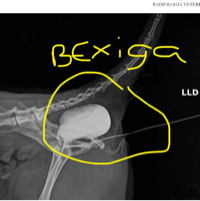

Pessoal, minha gatinha lola de 15 anos sofreu acodente no sabado (9/11), ela esta internada desde sabado. Ela precisa fazer duas cirurgias: uma pra colocar a bexiga no lugar e pra corrigir a fratura da bacia.